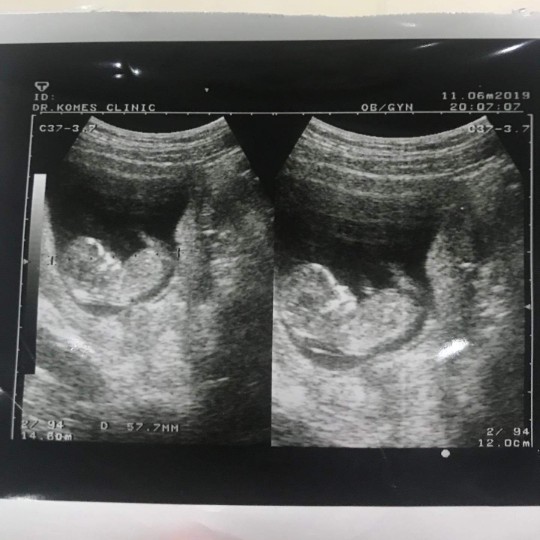

แม่บ้านนี้อยากได้ลูกสาวค่ะ #กำหนดคลอด 12 ธันวาคม #รูปซาวด์ตอน 12W

ซาวด์ตอน 12wค่ะ หมอบอกว่าแนวโน้มผู้ชายมีแหลมๆโด่มาเชียว